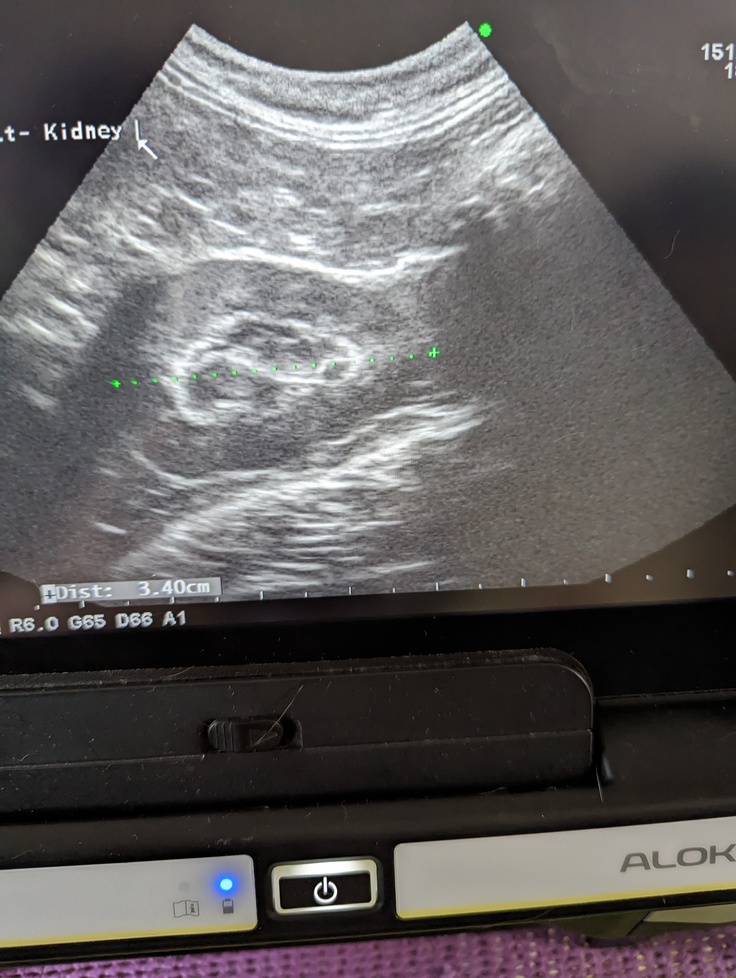

エコー検査は、くるくる回しながら説明してくれるのですが、説明がなければ全部同じように見えるので、それを判断するお医者さんは凄いなぁ…といつも思います。

【病院から掲載の許可を得ています】